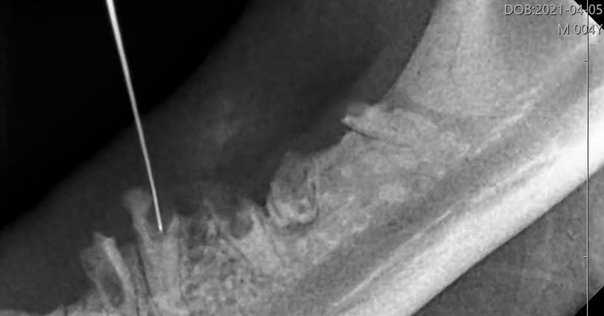

HOT ! インプラント時代に見直す 歯の自家移植を始めよう!―歯根完成歯の長期経過症例か… インプラント時代に見直す歯根膜の活用 歯の自家移植を始めよう

インプラント時代に見直す 歯の自家移植を始めよう!―歯根完成歯の長期経過症例か… インプラント時代に見直す歯根膜の活用 歯の自家移植を始めようの詳細情報

インプラント時代に見直す歯根膜の活用 歯の自家移植を始めよう。インプラント時代に見直す 歯の自家移植を始めよう!―歯根完成歯。インプラント時代に見直す歯根膜の活用 歯の自家移植を始めよう。書評『インプラント時代に見直す歯根膜の活用 歯の自家移植を。。「インプラント時代に見直す 歯の自家移植を始めよう!―歯根完成歯の長期経過症例から考える要点―」甲田和行定価: ¥ 16000#甲田和行 #本 #自然/医療・薬学・健康

• インプラント時代に見直す歯根膜の活用 歯の自家移植を始めよう

• インプラント時代に見直す 歯の自家移植を始めよう!―歯根完成歯

• 書評『インプラント時代に見直す歯根膜の活用 歯の自家移植を